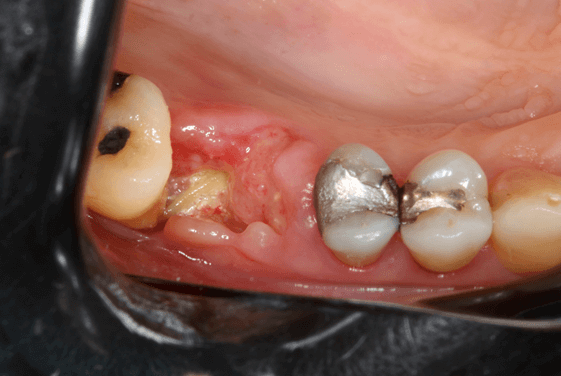

A preservação do alvéolo é uma opção de tratamento, evitando ou reduzindo a perda óssea. Alguns procedimentos são sugeridos com o objetivo de reduzir essa perda fisiológica, como a utilização de biomateriais preenchendo o alvéolo, barreiras, instalação de implante imediato entre outros. 4

Avaliamos o desempenho do biomaterial de hidroxiapatita com colágeno tipo I (Extra Graft XG-13®) na manutenção do volume alveolar.

A aplicação como o caso clínico abaixo se mostrou uma técnica acessível a todos cirurgiões dentistas, pois se trata de um procedimento de simples execução e acessível. Logo, deveria constar na clínica diária.